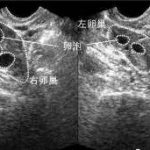

众所周知,试管婴儿手术是一项无论是实验环境,还是医生技术等要求都是比较高的,而三代试管手术更甚。所以,国内能开展植入前胚胎遗传诊断技术的机构不算太多,其中有3家位于南京省。其解决了众多有遗传疾病的家庭生育难题,那么,2023年南京究竟有哪些三代试管婴儿医院呢,其成功率排名,和收费情况如何,一起来看看。

南京有医院支持三代试管技术